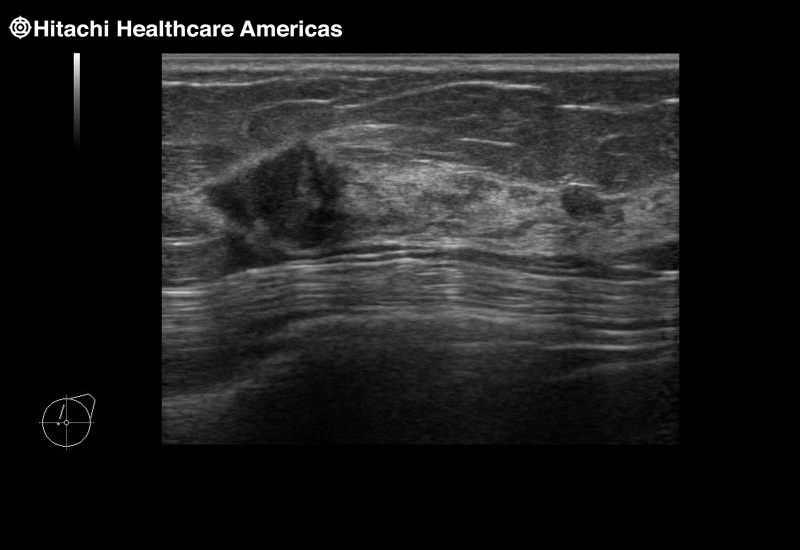

Fujifilm Healthcare's dedication to Surgeons provides outstanding ultrasound technology, professional support and the specialized tools necessary to best perform comprehensive real-time ultrasound imaging in Breast Surgery, General Surgery, Laparoscopic Surgery, Neurosurgery, Robotic Surgery and Surgical Oncology.

Recognized for our outstanding image quality, outstanding system reliability and intuitive use of cutting edge technology, Fujifilm Healthcare remains the standard in the field of Surgery.

Recognized for our outstanding image quality, outstanding system reliability and intuitive use of cutting edge technology, Fujifilm Healthcare remains the standard in the field of Surgery.